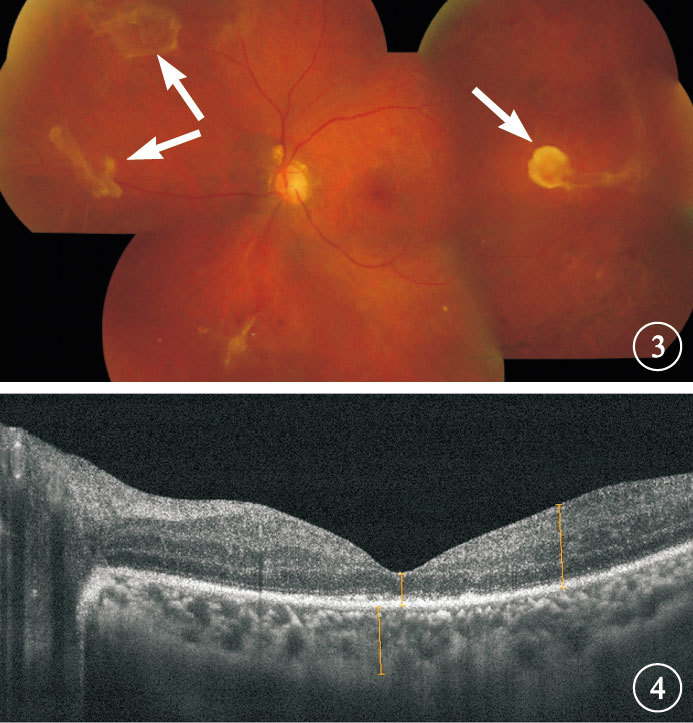

均行最佳矯正視力(BCVA)、眼壓、裂隙燈顯微鏡、間接檢眼鏡、B型超聲、眼底彩色照相、光相干斷層掃描檢查。患眼平均BCVA 0.03±0.25。數指及以下者18只眼,占36.0%;<0.1者15只眼,占30.0%;0.1~0.3者16只眼,占32.0%;>0.3者1只眼,占2.0%。BCVA數指及以下者18只眼中,光感者3只眼,手動者4只眼,數指者11只眼。TRD累及黃斑16只眼,其中廣泛視網膜脫離4只眼(圖 1,2);未累及黃斑34只眼。TRD累及黃斑的16只眼BCVA為光感~0.05,其中數指及以下9只眼;平均BCVA 為0.01±0.36。未累及黃斑的34只眼BCVA為手動~ 0.5,其中數指以下9只眼;平均BCVA為0.05±0.30。兩者BCVA比較,差異有統計學意義(t=-4.841,P<0.01)。

圖1

患眼彩色眼底像。后極部大面積纖維增生膜伴視網膜前出血??圖 2 圖 1患眼B型超聲像。玻璃體內條狀光帶,與視盤相連,光帶呈中強回聲,光帶下可見密集點狀回聲

均行最佳矯正視力(BCVA)、眼壓、裂隙燈顯微鏡、間接檢眼鏡、B型超聲、眼底彩色照相、光相干斷層掃描檢查。患眼平均BCVA 0.03±0.25。數指及以下者18只眼,占36.0%;<0.1者15只眼,占30.0%;0.1~0.3者16只眼,占32.0%;>0.3者1只眼,占2.0%。BCVA數指及以下者18只眼中,光感者3只眼,手動者4只眼,數指者11只眼。TRD累及黃斑16只眼,其中廣泛視網膜脫離4只眼(圖 1,2);未累及黃斑34只眼。TRD累及黃斑的16只眼BCVA為光感~0.05,其中數指及以下9只眼;平均BCVA 為0.01±0.36。未累及黃斑的34只眼BCVA為手動~ 0.5,其中數指以下9只眼;平均BCVA為0.05±0.30。兩者BCVA比較,差異有統計學意義(t=-4.841,P<0.01)。

圖1

患眼彩色眼底像。后極部大面積纖維增生膜伴視網膜前出血??圖 2 圖 1患眼B型超聲像。玻璃體內條狀光帶,與視盤相連,光帶呈中強回聲,光帶下可見密集點狀回聲